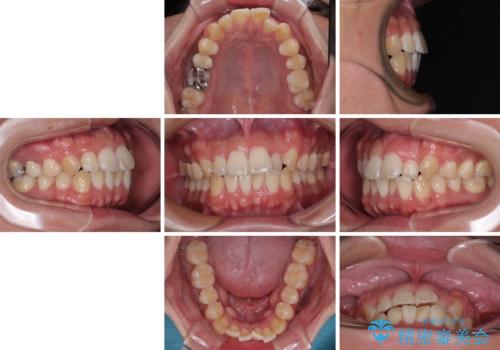

前歯のデコボコをささっと治す 短期間でのインビザライン矯正治療

- 前歯の反対咬合などを気にして来院された患者様です。

ワイヤー矯正、マウスピース矯正どちらでも対応可能であったので、ご本人の希望によりインビザラインにて矯正治療を行うこととしました。

毎日の装着時間をしっかりと守ってくださり、1年強の短期間で、あっという間に治療を終えることができました。